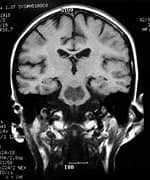

By sheer serendipity, many years ago Dr. Gordon provided care for a young man with a history of numerous sports-related head injuries, whose parents were themselves patients at the clinic. The young man's symptoms long outlasted the immediate effects of his acute injury and included loss of concentration, memory, mental energy, focus, and physical well-being, often accompanied by loss of lean muscle mass and an increase in body fat. The parents, familiar with the effects of hormonal imbalances, naturally assumed that their son's problems might reflect an endocrine problem of his own. And indeed, many of his symptoms resembled those of adult patients with so-called hypopituitarism, or loss of pituitary gland function. The pituitary gland is located at the base of the brain and is sometimes called the "master" gland of the endocrine system, because it controls the functions of the other hormone- secreting glands. Gordon, who is nothing if not intellectually curious, hit the books. What he found was startling and life-changing, for himself as a clinician, for his young patient, and now for scores of additional victims of traumatic brain injury. Symptoms of Traumatic Brain Injury Mimic Pituitary DysfunctionDr. Gordon found a wealth of published literature suggesting that traumatic brain injury causes pituitary dysfunction, confirming his initial hunch.1 Although the figures vary between studies, at least 50% (and up to 76%) of traumatic brain injury victims show some loss of pituitary hormone function immediately after the brain injury.2-4 In general, the more severe the original brain injury, the more profound the hormonal deficits, although hormone deficiency or insufficiency (levels in the low "normal" range) are seen even in patients with mild traumatic brain injury.5-9 And while about 58% of patients recover their normal pituitary function within one year of their head injury, a shocking 52% develop new pituitary hormone deficiencies after one year. 10,11 Those deficits include reductions in many different pituitary hormones, including those that regulate the thyroid gland, the adrenal glands (that produce cortisol, DHEA, and other vital hormones), the gonads (where estrogen and testosterone are produced), and growth hormone.3,4,12,13 The severity of the hormone deficiencies correlates strongly with the kinds of symptoms Dr. Gordon was seeing in his patient. For example, patients with growth hormone deficiency or insufficiency had significantly worse disability rating scores, greater rates of depression, worse quality of life, lower energy, greater fatigue, and poorer emotional well-being, compared to brain injury patients with normal hormonal levels.14,15 Dr. Gordon's hunch was borne out: patients with traumatic brain injury often have pituitary hormone deficiencies or insufficiencies, especially in growth hormone. And those defects are closely associated with the persistent neurological, psychological, and emotional deficits that are so tragically common in survivors of traumatic brain injury. And where are you most likely to find a high concentration of survivors of traumatic brain injury? The United States military.

Growth Hormone: A Critical PlayerGrowth hormone is the most common hormone deficiency or insufficiency in patients with traumatic brain injury at any level of severity.16-19 Deficiencies in this hormone are especially marked in patients with moderate to severe traumatic brain injury.20 Brain-injured patients with growth hormone deficiency experience rapid weight gain and have substantially lower levels of other hormones as well.17,19 Low growth hormone levels are also associated with excessive anxiety and depression and poor physical health and quality of life.15,21 Finally, brain-injured patients with growth hormone deficiency show greater deficits in attention, executive functioning, memory, and emotion than those with normal growth hormone levels.22 Growth hormone is an intriguing hormone, and we are learning more about it each year. In children, it is responsible for regulating linear growth, ultimately determining adult height and body proportions. But growth hormone has many other remarkable functions throughout the body and into adulthood. It is neuroprotective, increasing survival of damaged nerve cells and promoting regeneration of nerve tissue.23-25 Growth hormone also increases the number of receptors for other hormones in tissues throughout the body; this has the effect of increasing the body's sensitivity to those hormones' actions, helping to overcome the effects of their deficiencies.26-29 Like all hormones, growth hormone acts by binding to specific cell-surface receptors. Receptors for growth hormone are found throughout the brain, and they are especially densely distributed in brain regions responsible for learning and memory.30,31 That may explain why declining growth hormone levels are associated with poorer cognitive function. Growth hormone levels fall with age and are especially low in Alzheimer's disease.32-36 As Dr. Gordon points out, it is therefore not surprising that traumatic brain injury patients often show symptoms identical to the cognitive decline and memory loss we see with aging and Alzheimer's disease. In essence, a brain-injured patient with low growth hormone levels undergoes accelerated cognitive aging. Hope for Traumatic Brain Injury Patients at Millennium Health Centers